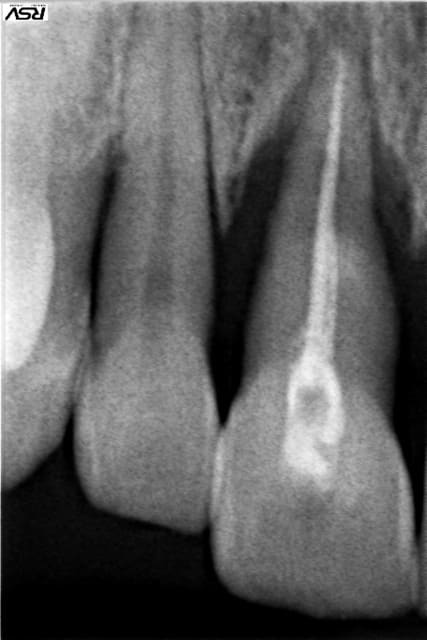

Voici la radio avant. Après extraction j'ai pu constater (ce dont je me doutais un peu) que la résorption externe de la dent s'étendait du collet (juste en dessous) jusqu'à 2 mm de l'apex. A ma connaissance, lors d'une résorption radiculaire, il n'y a plus de fibres desmodontales, et donc aucun espoir de ré-attache, même avec greffe.

Tu aurais une pano ? Au vu de la radio de la latérale, l'implant avec greffe dans ce contexte n'est peut être pas une bonne idée.

Vu le profil décrit (fumeuse, moindre coût, motivation bof, ....) et - puisqu'on a que ça - la rétro : laisse tomber l'implanto.

Reste le bridge conventionnel ou collé. Sans compter qu'un peu de paro ne ferait pas de mal. Mais, comme dit plus haut, il manque des informations (la 21 pour commencer).